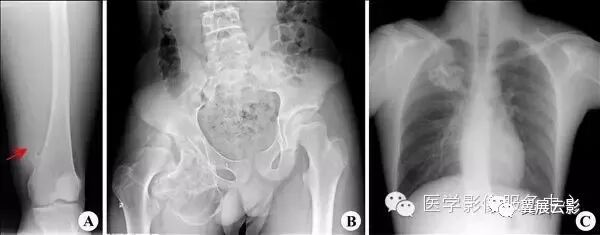

【普通放射图片】:

【影像表现】:X线股骨正位(A)示股骨下端骨性突起(↑);X线骨盆正位(B)示右侧耻骨呈结节状突起;X线锁骨正位(A)示右侧锁骨呈菜花状突起。【影像诊断】:骨软骨瘤。